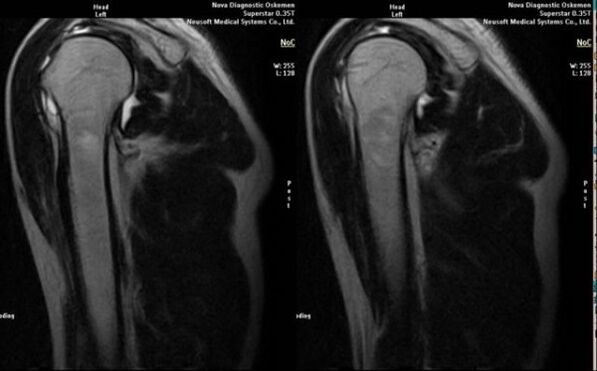

- magnetinis rezonansas ir kompiuterinė tomografija;

Požymiai, tiesiogiai rodantys artrozės vystymąsi, yra reikšmingas sąnario tarpo susiaurėjimas, subkremzlinių struktūrų sklerozė, paties chondrocitų sluoksnio plonėjimas, osteofitų atsiradimas ir druskos kristalų nusėdimas intraartikuliniame skystyje.